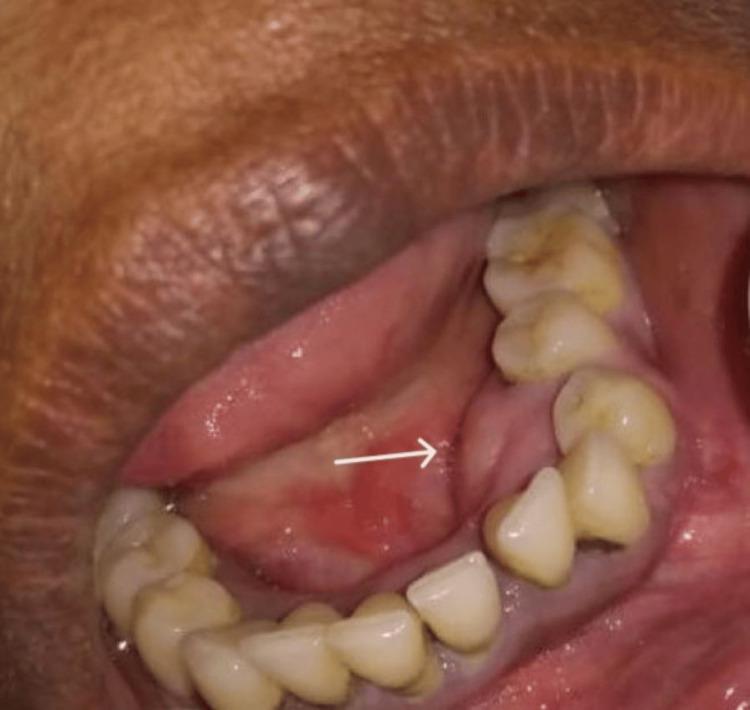

Benign osseous tumors of mesodermal origin that are included within the group of fibro-osseous lesions include cemento-ossifying fibromas (COFs). The fibrocellular component of these diseases originates from the periodontal ligament, which deposits bone and cementum encased in fibrous tissue. It typically appears in the mandible and presents as a solitary, nonaggressive, slowly developing, asymptomatic, expansile lesion, rarely occurring in the maxilla. The only intervention that proved to be successful in producing excellent outcomes and that may be regarded as a final therapeutic option is the complete surgical removal of COFs. Presenting herein is a case report describing a painless and expansile mass in the left mandibular region, histopathologically diagnosed as COF.

中胚层起源的良性骨肿瘤,属于纤维-骨病变组,包括牙骨质化纤维瘤(COF)。这些疾病的纤维细胞成分起源于牙周膜,该膜会在纤维组织包裹下沉积骨和牙骨质。它通常出现在下颌骨,表现为孤立、无侵袭性、发展缓慢、无症状的膨胀性病变,很少发生在上颌骨。唯一被证明能产生良好效果且可被视为最终治疗选择的干预措施是完整手术切除COF。本文呈现了一例病例报告,描述了左下颌区域一个无痛性膨胀性肿块,经组织病理学诊断为COF。